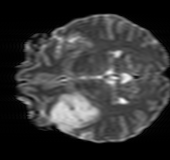

λT1=6.63subscript𝜆subscript𝑇16.63\lambda_{T_{1}}=6.63 Refer to caption (a) 34.38/0.9371 Refer to caption (b) 42.42/0.9883 Refer to caption (c) 44.60/0.9920 Refer to caption (d) 45.50/0.9940 Refer to caption (e) PSNR/SSIM

λT2=2.11subscript𝜆subscript𝑇22.11\lambda_{T_{2}}=2.11 Refer to caption (f) 29.74/0.8903 Refer to caption (g) 36.25/0.9734 Refer to caption (h) 36.42/0.9752 Refer to caption (i) 37.70/0.9832 Refer to caption (j) PSNR/SSIM

λflair=8.00subscript𝜆𝑓𝑙𝑎𝑖𝑟8.00\lambda_{flair}=8.00 Refer to caption (k) 39.89/0.9311 Refer to caption (l) 43.94/0.9864 Refer to caption (m) 44.74/0.9883 Refer to caption (n) 45.49/0.9894 Refer to caption (o) PSNR/SSIM

Figure 3: Visual comparison of different methods, with PSNR (dB) and SSIM values listed under the images. After recovery, the images are shaper with more visible details.